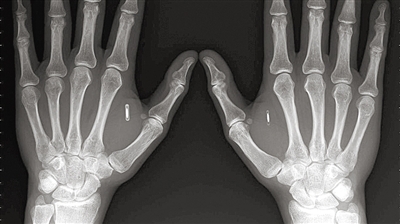

植入芯片的设计都非常小,阿马尔在自己双手上各植入了一个射频识别芯片。

图片来源:techinsider.io

阿马尔在自己双手上各植入了一个射频识别芯片。现在他不但摆脱了各种钥匙,还摆脱了各种密码。镶嵌在身体里的芯片可以自动帮阿马尔开门、锁门、在电脑上输入密码。他甚至把摩托车和汽车跟芯片连接在一起,这样连启动摩托车和汽车时也不需要使用钥匙了。